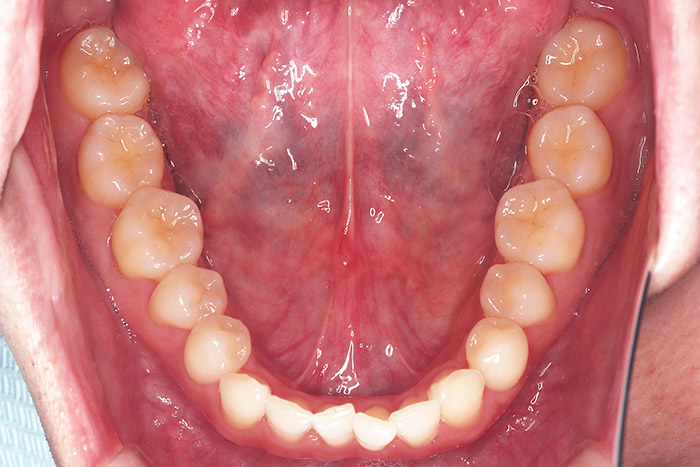

A様

治療前

before

年齢 31歳

性別 女性

治療名称 マウスピース型カスタムメイド矯正歯科装置(インビザライン)・コンプリヘンシブパッケージ(難症例)

総額治療費用 935,000円(税込10%) 金額備考 精密検査料・診断料 33,000円(税込10%)

治療期間 3年4か月 通院頻度など 1か月ごと(途中から3~4か月ごと)

患者の症状 叢生、正中のずれ、上顎左右側切歯の口蓋側転位(交叉咬合)

治療方法 非抜歯で、マウスピース型カスタムメイド矯正歯科装置(インビザライン)による矯正

歯列弓を拡大することで非抜歯を可能にしました。

治療結果 側切歯の交叉咬合は解消、上下正中のずれも改善し咬み合わせが良くなりました。